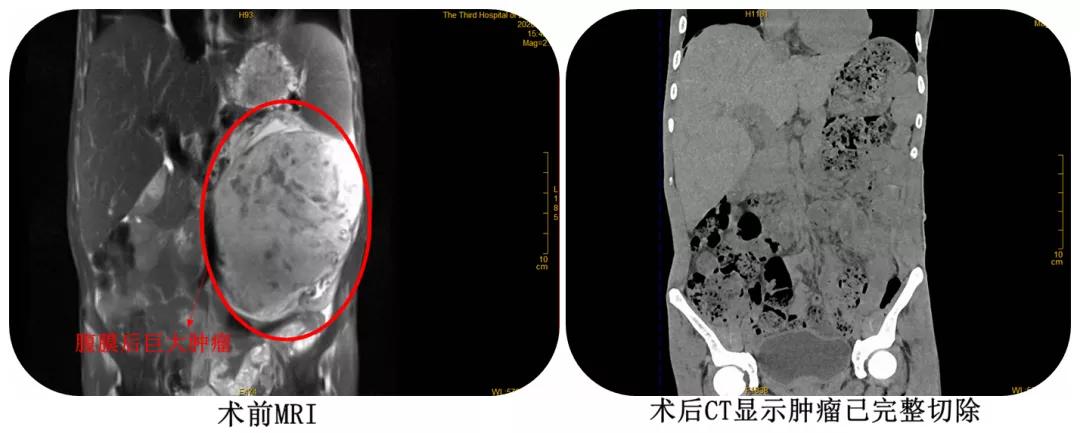

一年前,42岁的陈先生发觉自己脖子变粗,以为只是甲亢,就没当回事。直到今年2月初,陈先生开始出现手抖、心悸、心慌,腹部胀痛、发热不退等现象,正值疫情期间,这可把家人都吓坏了,急忙将陈先生送往漳州市第三医院就诊。陈先生到达医院体温显示39.8℃,立即被转入发热门诊,胸腹MRI检查结果发现,患者双肺结核活动期伴感染(引起发热不退),且肚子里长了个巨大肿瘤!这颗巨大的腹膜后肿瘤占满整个腹腔,随时可能出现生命危险,医生建议尽快手术治疗。

术中发现,患者肿瘤上极与脾脏胰尾紧密粘连,下极压迫、侵犯左肾,至左肾萎缩、变型,肿瘤内侧超过腹主动脉,且肿瘤血供丰富,给手术增加很大难度。好在手术团队准备充分,凭借着丰富的经验,沉稳应对,历经4.5小时,术中输血2200ml,最终有惊无险地顺利完成手术。术后,转入ICU观察治疗两天,待病情稳定后转入普通病房,在泌尿一科医护人员的细心救治下,目前患者恢复良好。病理显示为:孤立性纤维性肿瘤(低度恶性),后期需随访复查,并进行结核治疗及甲亢治疗!

(巨大肿瘤完整切除)